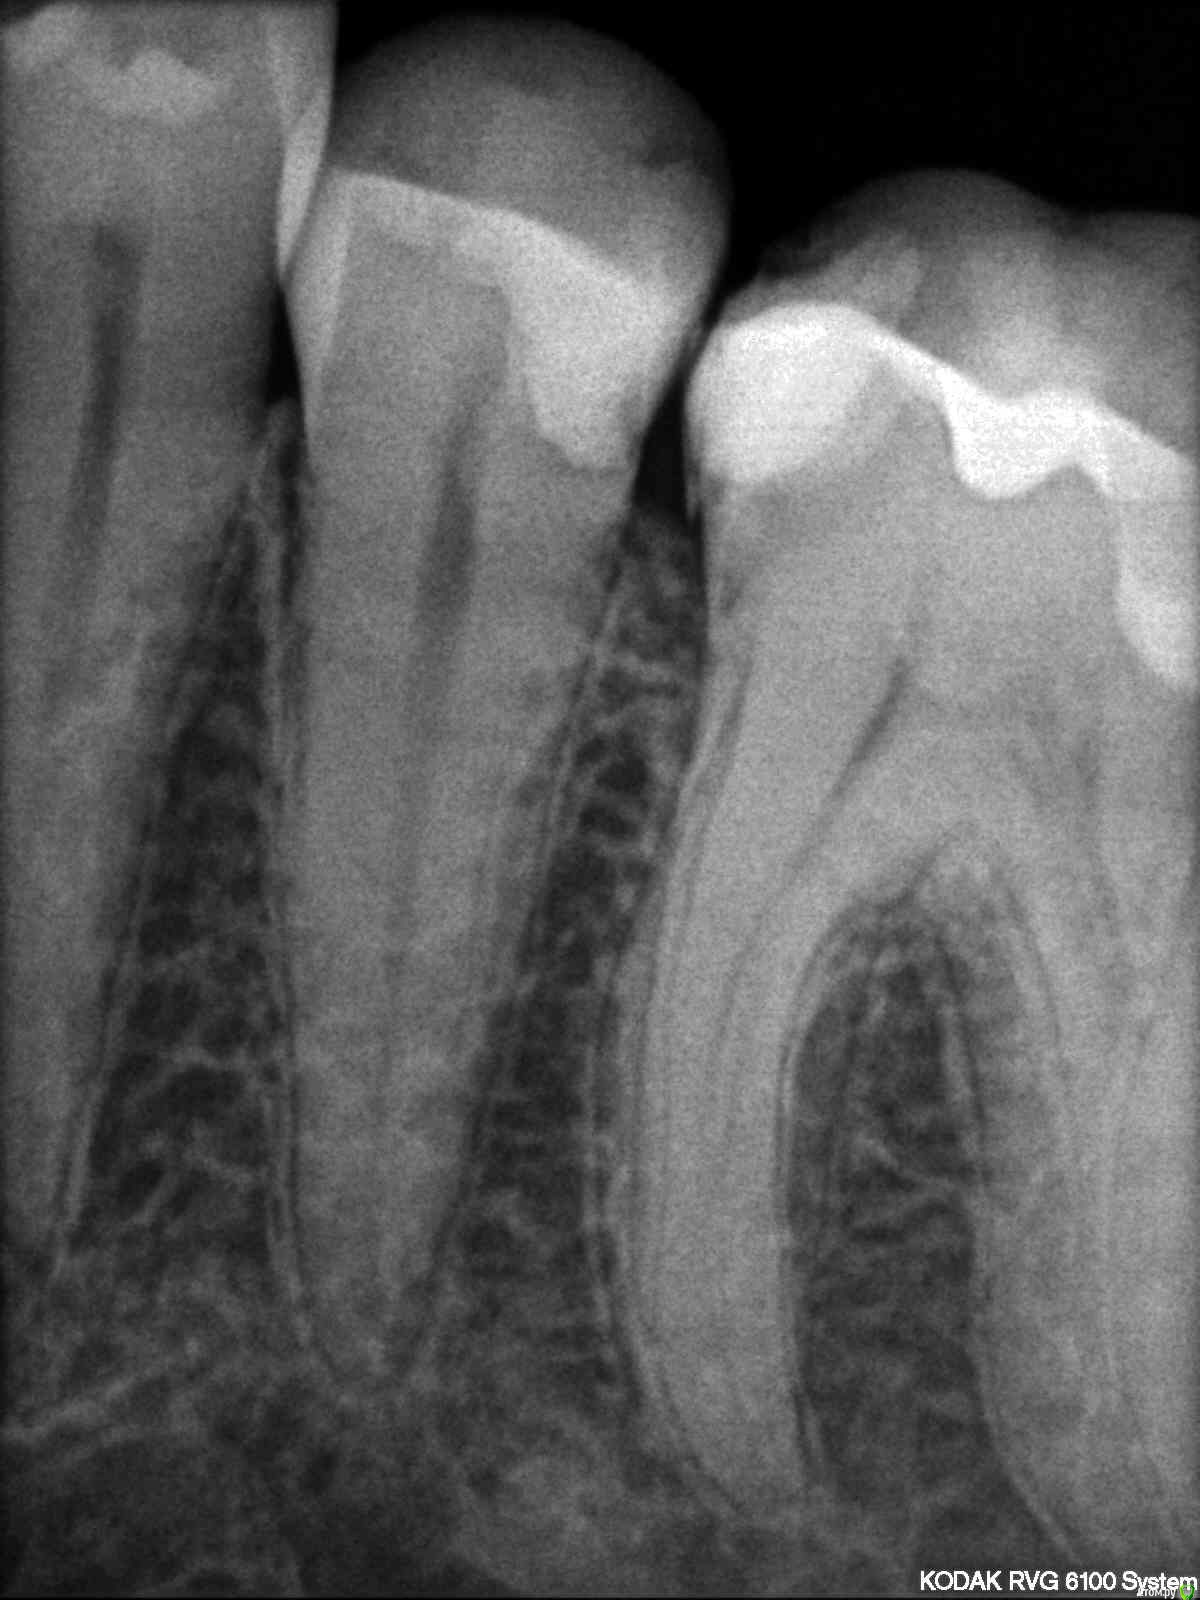

iamme Опубликовано 3 мая, 2017 Поделиться Опубликовано 3 мая, 2017 Все началось с того, что попал орех между 35, 36, увеличилось расстояние и стала застревать пища. В 35 зубе уже переделывали пломбу года 4 назад, чтобы восстановить контактный пункт, и вот опять. Стоит ли оставить все как есть или надо лечить? Я сходила просто на профилактический осмотр в свою клинику, врачу показалось, что с контактным пунктом более менее ок. Снимок не делали. Сказали лечить средний кариес на верхнем клыке (там вообще нет пломбы). Тогда сходила в другую, врач сделал снимок, сказал, что в 6 возможно пульпит, а в 5 кариес - надо лечить сначала 6. А клык менее важен (со средним кариесом согласился) В третьей сказали, что наоборот: в 6 кариес, а в 5 пульпит. Сначала 5. Надо сказать, лечить я лишний раз боюсь, так как уже напрасно пролечила один зуб. Вопрос к вам, надо ли что-то лечить, и что в первую очередь? Прикладываю снимок 35,36 Ссылка на комментарий

Pan Опубликовано 3 мая, 2017 Поделиться Опубликовано 3 мая, 2017 (изменено) порой удивляет осведомленность в терминах некоторых пациентов похвальнос. В 36 желательно переделать контактный пункт с восстановлением анатомического образования - межбугоркового валика в месте контакта с 35. Пломба в 35 также требует замены. Что бы подтвердить диагноз пульпита, данных не достаточно, нужны сбор анамнеза и дополнительные методы обследования. Изменено 3 мая, 2017 пользователем Pan 1 Ссылка на комментарий

St. Опубликовано 3 мая, 2017 Поделиться Опубликовано 3 мая, 2017 Нет, вы не совсем правильно поняли. Контакт это 2 зуба - в Вашем случае 5 и 6, чтобы не застревала еда на обоих контактирующих зубах должны быть правильные выпуклые поверхности, без острых нависающих краев. На 6 пломба есть и форма правильная. На 5 пломба со сколом и кариесом. Поэтому и застреет.Если 5 оставить как есть , то кариес на нем пойдет глубже.и если сейчас вероятность лечить\не лечить канал грубо говоря 50/50, то потом точно придется лечить каналы. Вы сами стали бы себе лишний раз зуб (5-ку) пилить в данной ситуации? Я сама себе зубы не пилю, у меня есть доктор , которому я доверяю. А вообще зубы Ваши, соответственно решение принимать Вам 1 Ссылка на комментарий